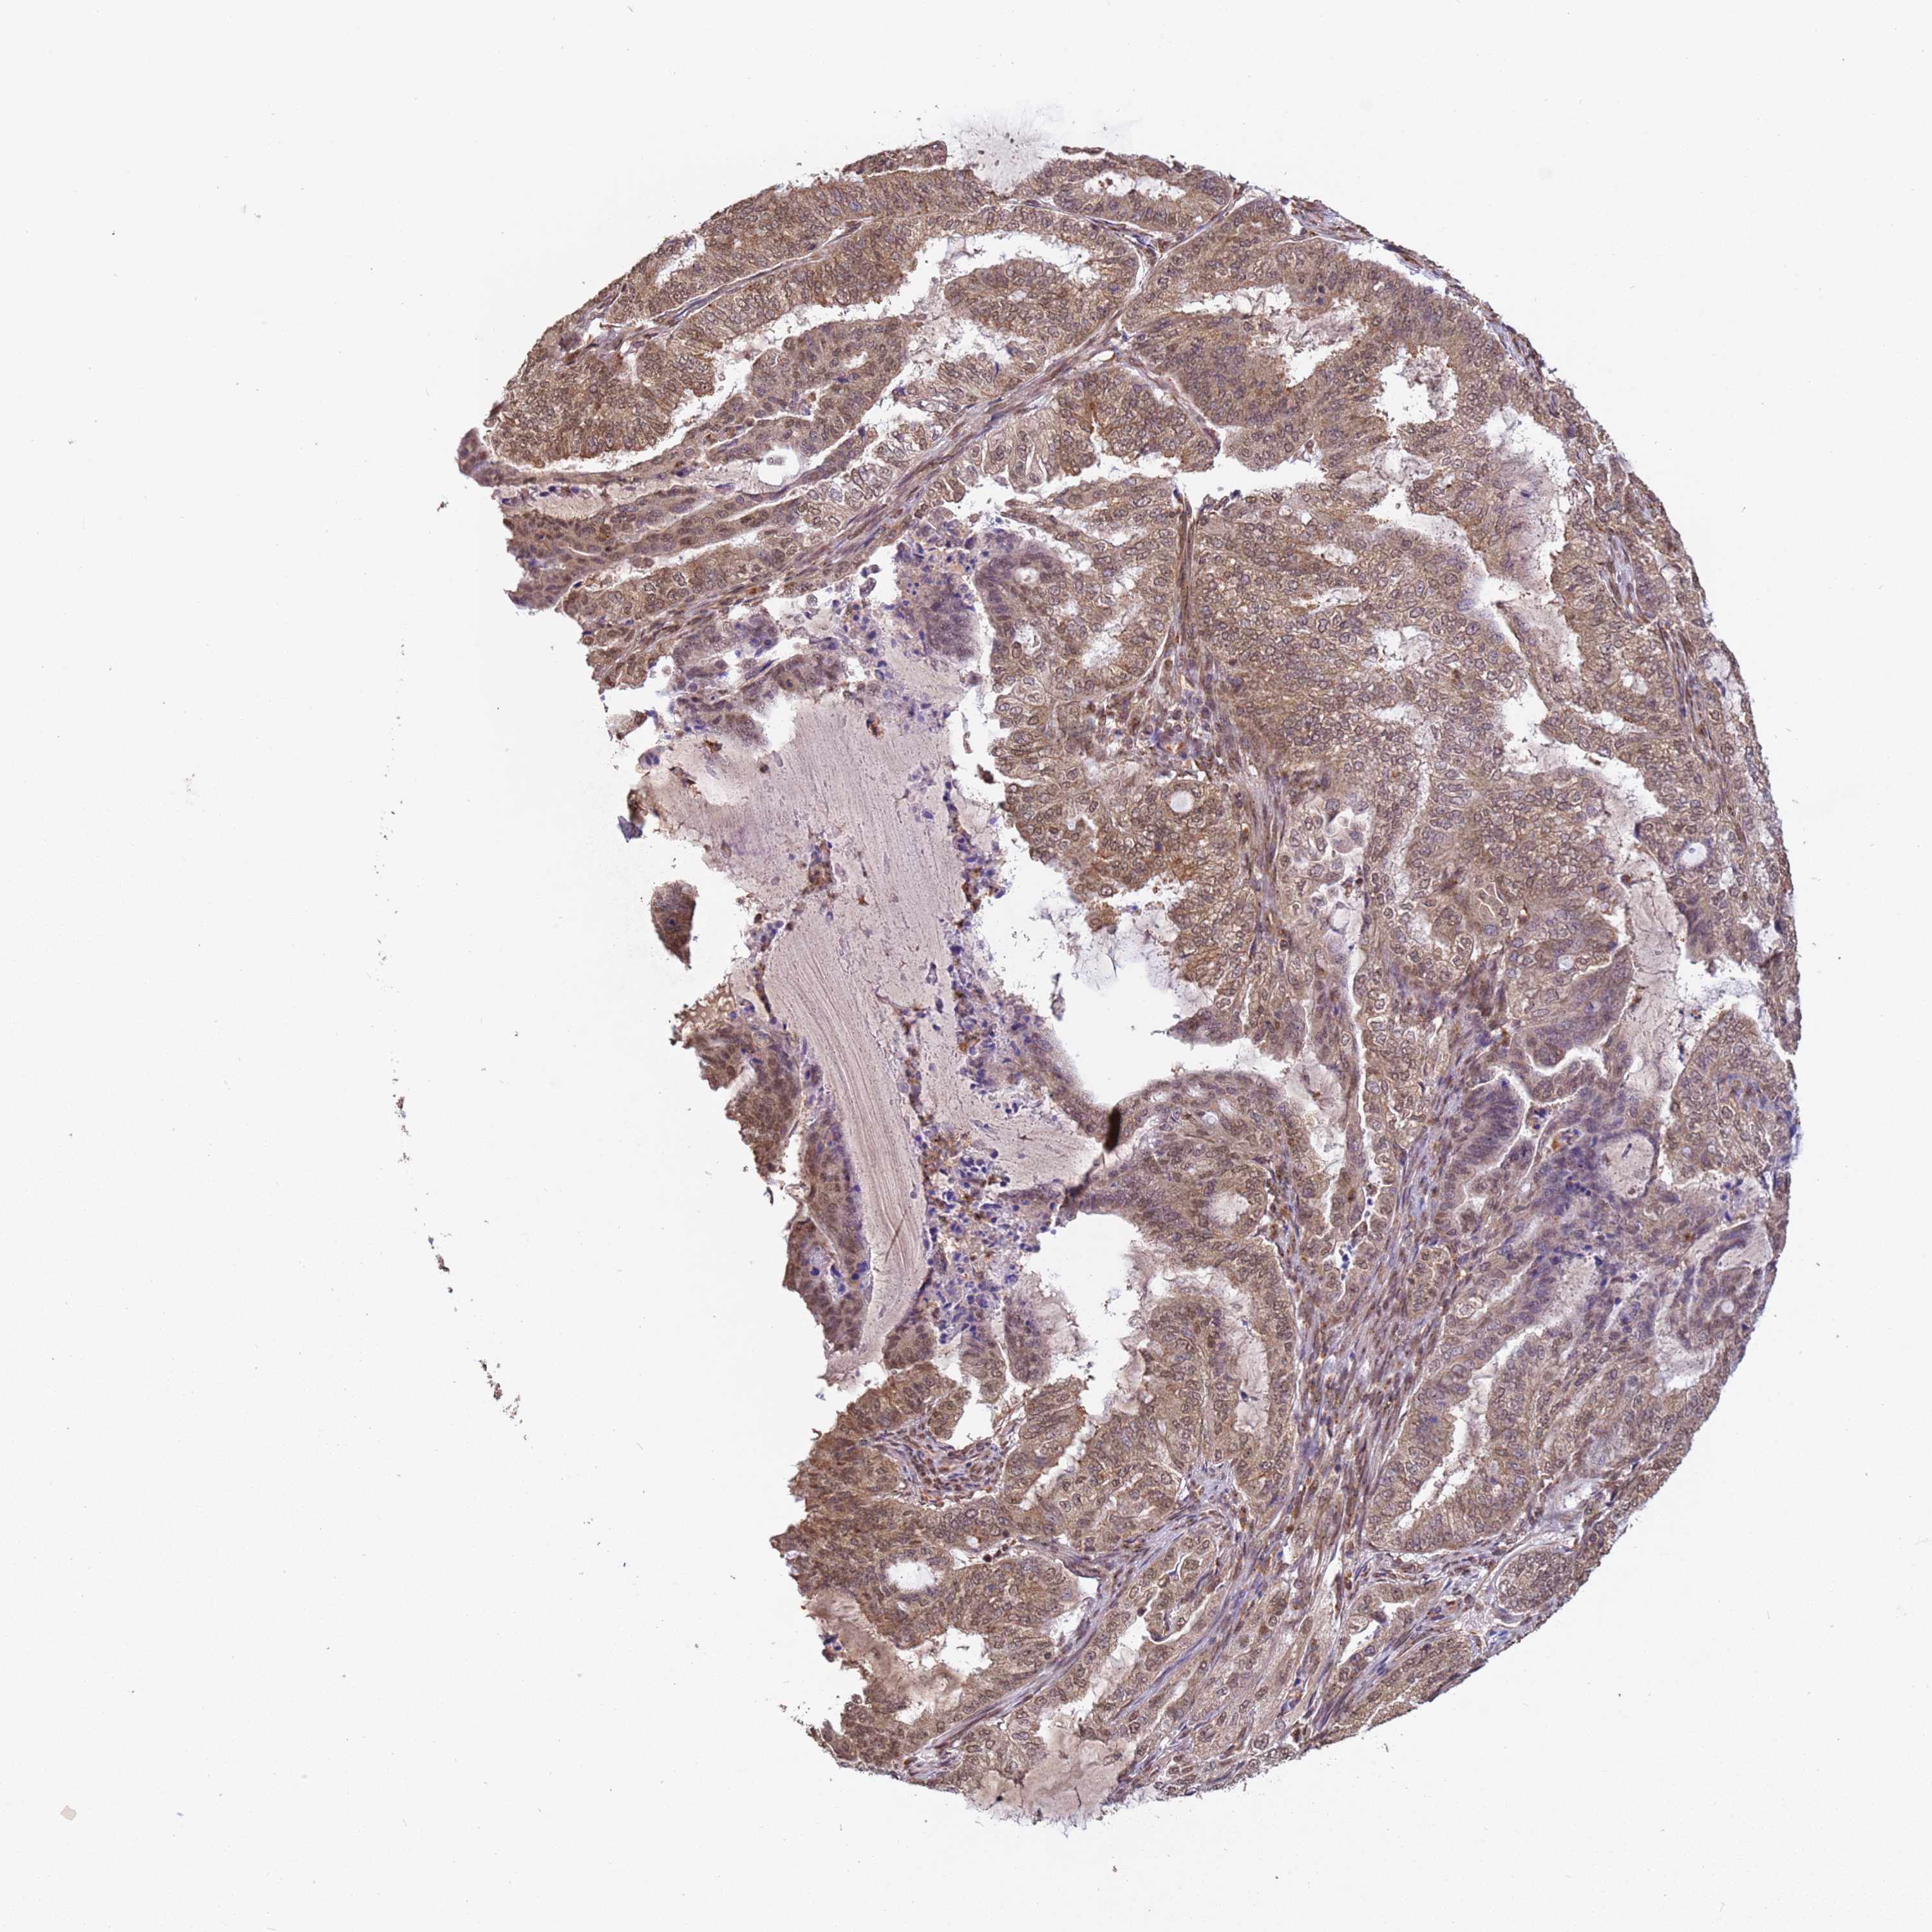

ENDOMETRIAL CANCER - Protein expressioni

A mouse-over function shows sample information and annotation data. Click on an image to view it in a full screen mode. Samples can be filtered based on level of antibody staining by selecting one or several of the following categories: high, medium, low and not detected. The assay and annotation is described here.

Note that samples used for immunohistochemistry by the Human Protein Atlas do not correspond to samples in the TCGA dataset.

Antibody stainingi

Antibody staining in the annotated cell types in the current human tissue is reported as not detected, low, medium, or high, based on conventional immunohistochemistry profiling in selected tissues. This score is based on the combination of the staining intensity and fraction of stained cells.

Each image is clickable and will lead to virtual microscopy that enables deeper exploration of all samples and also displays staining intensity scores, fraction scores and subcellular localization as well as patient and tissue information for each sample.

Antibody HPA045624

Staining

High

Medium

Low

Not detected

Intensity

Strong

Moderate

Weak

Negative

Quantity

>75%

75%-25%

<25%

None

Location

Nuclear

Cytoplasmic/membranous

Cytoplasmic/membranous,nuclear

Adenocarcinoma, NOS